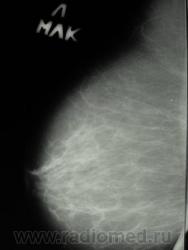

пациентка после травмы молочной железы, с 26.02.09 предъявляет жалобы на кровянистые выделния из правого соска. Осмотрена онкологом- посттравматическая гематома правой молочной железы, ПАБ материал получен из очага кровоизлияния. Делала мамографию, заключение из другой больницы- узловая фиброзная мастопатия правой молочной железы. А на УЗИ- дилятация мелких протоков в правой молочной железе, склерозированный лимфоузел в наружной области справа 11 на 5 мм. На данный момент беспокоят все те же выделения из правого соска, напрвили к нам на маммографию, боятся онкологию пропустить. Ваше мнение коллеги?

последние 3 снимка-архив 28.05.09 г. Женщина 1935 г.р.

И вот, вышло такие две серии:

А, ведь, какая-то "объёмка" вырисовывается.